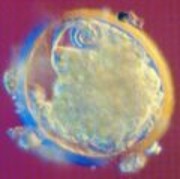

卵子的外層被一層透明的薄膜保護著,這使它看起來像一個懸浮在天體中的漂亮的星球。此時經過種種障礙的精子終於與卵子相遇,卵子外膜成為它們第一道需要攻破的關卡。此時,精子們把頭鑽到卵子的外壁上,尾巴不斷拍打著,卵子則隨著精子尾部的運動緩慢地逆時針轉動。